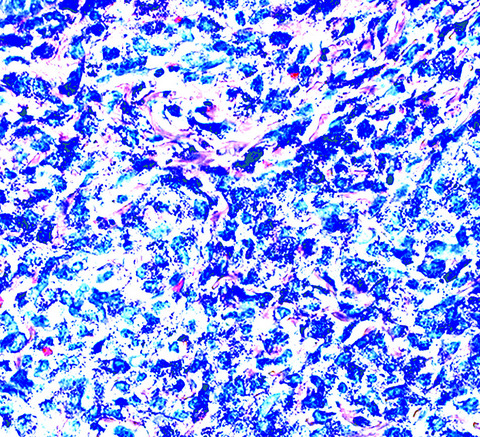

Positive stains

- Toluidine blue and Giemsa demonstrate metachromasia (granules are purple red)

- Leder (chloroacetate esterase), CD117 / c-kit

Microscopic (histologic) images